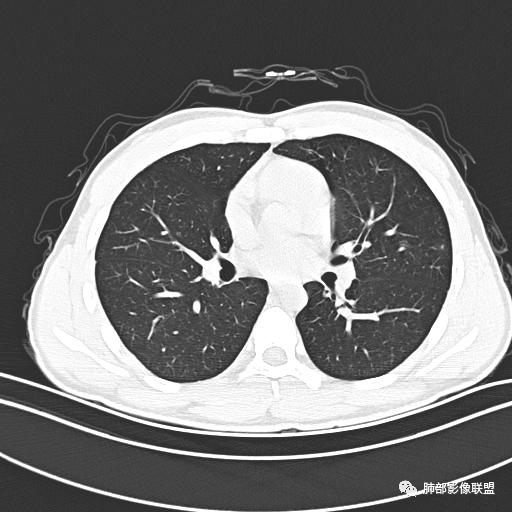

男,19岁

主  诉:发热、全身皮疹2天。

现病史:患者源于2天前受凉后出现发热,最高体温为38.5℃,且颜面部出现少量皮疹,无鼻塞、流涕、咳嗽、咳痰,未在意而未作特殊处理,次日全身皮疹逐渐增多至全身,伴轻度瘙痒,在当地卫生所给予抗病毒、抗感染治疗(具体用药不详)体温有所下降,但皮疹无明显消退,无腹痛、头痛,食欲无明显减退,为进一步诊治,遂于今日急来我院求治,患者目前精神尚可,体力正常,食欲正常,睡眠正常,体重无明显变化,大便正常,排尿正常。

小强:青年,发热,皮疹;双肺散在结节,周围磨玻璃,点晕征,疱疹病毒感染,鉴别荚膜组织胞浆菌,结核。 大雄:青年,急性起病,发热伴全身皮疹2天,抗病毒治疗体温有下降。双肺随机分布大小不等类圆结节,“点晕征”。考虑水痘-疱疹病毒(VZV)血播询问接触史,查体皮疹分布以及形态基本可诊断。 王开金江津中心医院呼吸科:青年男性,起病急,病程短,以发热,皮疹为首发症状,感染指标以单核细胞升高为主,胸部ct双肺多发结界,周围有晕,点晕表现,随机分布,同意於老师意见,水痘疱疹病毒血流感染累及肺。 王秀仙:双肺多发大小不等结节,周围有晕,边缘模糊,呈点晕征表现。青年,急性起病,发热伴全身皮疹2天,抗病毒治疗体温有下降。考虑疱疹病毒。鉴别荚膜组织胞浆菌。 傅昌瑜:19岁男性,发热、全身皮疹2天,单核细胞增高,双肺多发结节,结节边缘见边界不清磨玻璃影。点晕征+发热、全身皮疹+单核细胞增高——考虑水痘-带状疱疹病毒肺炎。 一切∮随缘:年轻男性,发热,皮疹两天,实验室,CRP,PCT增高,影像:双肺多发散在磨玻璃结节,边界欠清,大小不等,呈点晕征改变,以血管束周围分布为主,局部血管束略增粗,其它无明显改变,考虑:1:病毒性肺炎(水痘疱疹病毒?不知道皮肤有无改变)2:真菌(组织胞浆菌,血管侵袭性肺曲霉)3:GPA4:寄生虫(实验室没有看到嗜酸细胞增高) 赵山河:双肺散在结节,周围有晕,边缘模糊,呈点晕征表现。青年,急性起病,发热伴全身皮疹2天,抗病毒治疗体温有下降。考虑水痘—疱疹病毒感染。洪桥爱:青年男性,发热、皮疹2天,伴瘙痒,皮疹于面部首发,之后进展至全身,虽然没有对皮疹进行描述,但是从出疹时间及皮疹进展情况,伴瘙痒,应该就是个水痘患者;CT提示双肺随机分布结节影,部分结节伴有边界不清晕征,考虑水痘血播肺。 刘强:年轻男性,急性起病,皮疹,发热,抗感染治疗体温下降,说明有效。影像表现为散在点晕征,感染类疾病谱(疱疹病毒,真菌,结核),结合年龄,皮肤皮疹,考虑水痘-疱疹病毒性肺炎。 小兜:男性,19岁,发热皮疹两天,颜面部至全身,CRP,降钙素及单核增高。CT示双肺散在小结节,周围伴磨玻璃影,点晕征,考虑为水痘-带状疱疹病毒(varicella-zoster virus,VZV)肺炎 必有路:青年,皮疹+发热+“点晕征”→水痘-疱疹病毒(VZV) 许慧良:青年男性患者,发热、皮疹2天,体温最高38.5℃,第3天皮疹扩展至全身,伴瘙痒,胸部CT:双肺多发随机分布的小结节,结节周边见边界模糊的晕征,考虑水痘病毒感染流心明智:男,19,急性起病,发热伴全身皮疹2天。出疹顺序头→全身,抗病毒有效。胸部CT:两肺多发大小不等类圆形实性小结节影,随机分布,结节周围环绕GGO,边界模糊,呈点晕征。出疹特点是关键,未提示。考虑:血播病毒性肺炎,水痘-疱疹病毒?麻疹?鉴别荚膜组织胞浆菌、TB、血管炎、寄生虫等。 浪迹天涯:病灶多为5-10mm大小结节,结节周围可见磨玻璃样的晕环,常多发,可分布于肺内任何区域,考虑水痘—带状疱疹病肺炎如果短时间内有新的一个区域浸润,更加能说明,